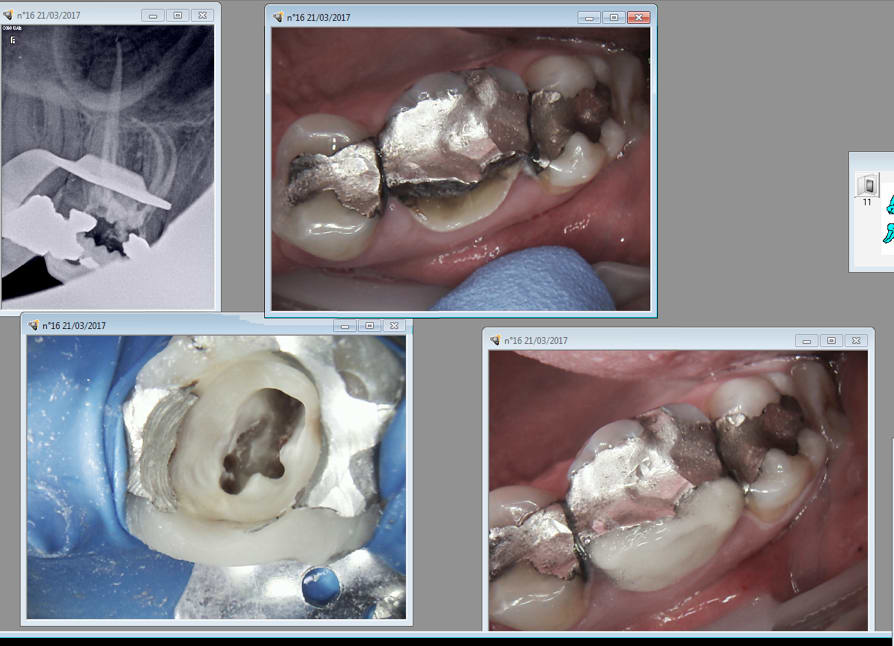

Ou là on ne joue pas dans la meme catégorie. Moi je fais des endos molaires à 80 balles en 25- 30 minutes. Cépaspareil. -)

Ca n'est qu'une question de séquence instrumentale. Avant il fallait etre doué , plus maintenant.

Celle là c'était ce matin 35 minutes parce que je me suis demandé pendant 10 minutes si il n'yavait pas un 3 ième mv. -)

Capture d écran 2017 03 21 22.27 - Eugenol

6szjws718sv1jksw54v4mpj3a6cu - Eugenol

Oui c'est ça, les endos de Chicot ne sont pas géniales, elles sont comme cela doit être (les dépassements de pâtes en moins mon Chicot ;-))

Mais pour la rapidité chapeau bas!

C'est vrai ne pas viser l'apex radiologique. -)

Mais je m'améliore , celle de 14 h. Nouveau patient ( mais est utile de le préciser quand on voit l'endo de 24, encore un problème technique hein ? ) ) Pulpite 25 ( signe d'appel status lol !) endo. Il va y avoir la 12 à reprendre non ? -)